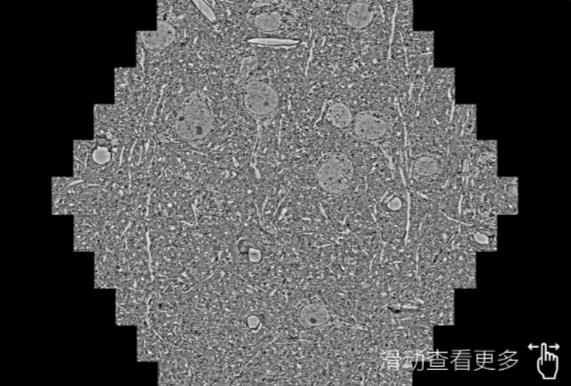

鼠脑切片。左图使用开封蔡司开封扫描电镜MultiSEM706对165μmx143pm面积区域成像,耗时仅需1.5秒。右图为鼠脑切片中30μm区域放大效果。样品由芝加哥大学B.Kasthuri提供。

使用蔡司高速开封扫描电镜MultiSEM对1mm²人脑皮层组织进行高分辨成像,并对其中的各种细胞结构进行三维重构分析。左图展示了2x3mm²组织平面中锥体神经元的三维重构效果。右图显示了局部体积神经元三维重构。图像由哈佛大学chtman实验室提供,渲染图由D. Berger 制作。